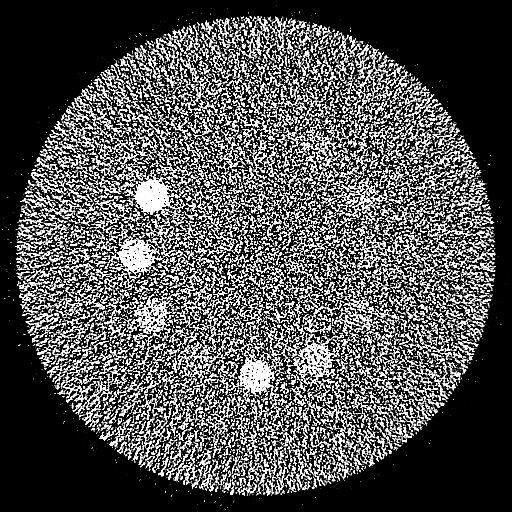

Deep Learning-based Mono-Energetic Images

(20-cm cylindrical phantom)